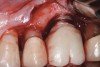

The results of these studies suggest that the shorter the prosthetic abutment height, the greater the amount of MBL that can be expected with bone-level implants (Figure 2). While these studies only measured MBL, it may be surmised that similar MBL patterns would develop on the facial and lingual aspects when the prosthetic abutment height is less than 2 mm. With greater MBL, the risk for bacterial colonization of the implant surface may increase. It would seem prudent, therefore, to place the crown margin in a position that would minimize MBL.

Fig 2. The height of this abutment was less than 2 mm on the facial. This may have led to additional marginal bone loss. Bacterial colonization of the abutment and the exposed implant body resulted in peri-implantitis.

Figure 2